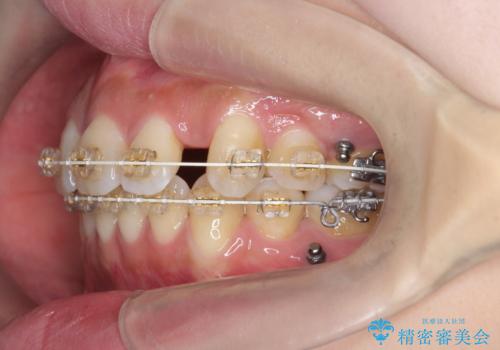

ガタつきと口元の改善 抜歯を伴うワイヤー矯正

- ワイヤー矯正

- 唇の閉じづらさと、前歯のがたつきの改善を希望され来院されました。

抜歯を行わなくてもなんとか並べられる歯並びですが、唇の閉じづらさをしっかりと改善するため抜歯を伴うマルチブラケット矯正を行うこととしました。